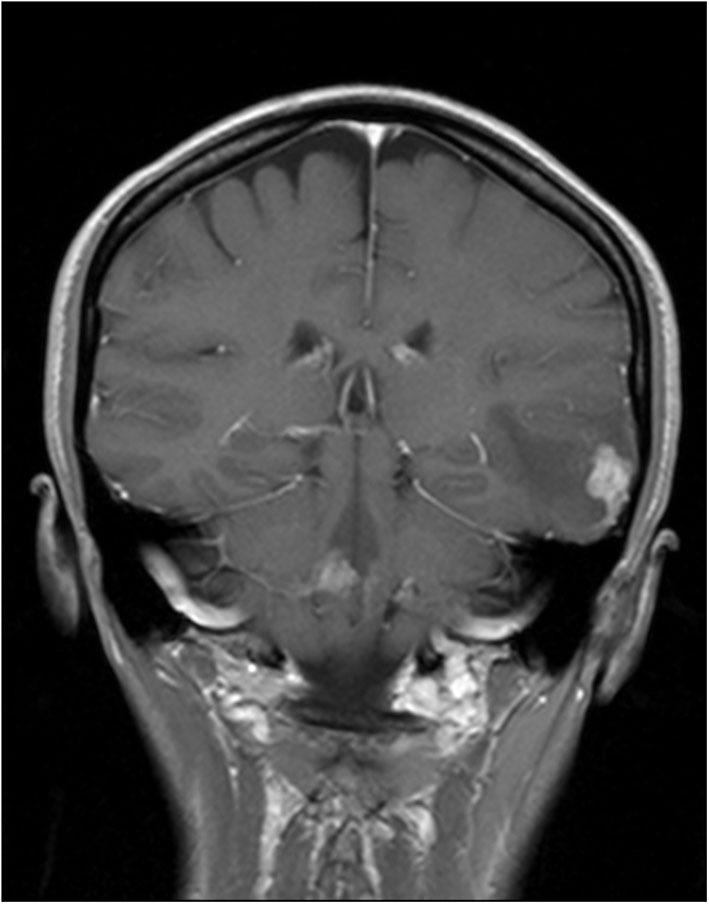

The involvement of the central nervous system (CNS) in Hodgkin lymphoma (HL) has been rarely reported, especially in its primary isolated form. Herein, we present a case of a 33-year-old woman, who received immunosuppressive treatment due to ulcerative colitis (at the beginning azathioprine and sulfasalazine, changed to mesalazine), with repetitive episodes of loss of consciousness for a few weeks and with no other symptoms. Magnetic resonance imaging scans of the head revealed a tumor in the lateral part of the left temporal lobe and in the cerebellum. Moreover, a subsequent computed tomographic scan of the chest revealed diffuse tumorous lesions in the lungs. The brain tumor was resected and a tumorous lesion resected from the lungs was biopsied. The histopathological analysis confirmed the final diagnosis of HL localized in the CNS with concomitant pulmonary lymphomatoid granulomatosis (LYG) grade 1. After the patient underwent radiotherapy and chemotherapy, the patient showed complete regression of lesions in the CNS and lungs, which was confirmed by positron emission tomographic scan. LYG and CNS-HL are rare proliferative disease derived from lymphocytes B and associated with EBV infections. An association between LYG and other autoimmune disorders has been reported, but to the best of our knowledge, this is the first case of the CNS-HL associated with lymphatoid granulomatosis.

中枢神经系统(CNS)受累于霍奇金淋巴瘤(HL)的情况鲜有报道,尤其是原发性孤立形式。在此,我们报告一例33岁女性病例,该患者因溃疡性结肠炎接受免疫抑制治疗(起初使用硫唑嘌呤和柳氮磺胺吡啶,后改为美沙拉嗪),数周内反复出现意识丧失,无其他症状。头部磁共振成像扫描显示左颞叶外侧和小脑有肿瘤。此外,随后的胸部计算机断层扫描显示肺部有弥漫性肿瘤病变。切除脑部肿瘤并对肺部切除的肿瘤病变进行活检。组织病理学分析证实最终诊断为CNS局限性HL并伴有1级肺淋巴瘤样肉芽肿病(LYG)。患者接受放疗和化疗后,正电子发射断层扫描证实CNS和肺部病变完全消退。LYG和CNS-HL是源自B淋巴细胞且与EB病毒感染相关的罕见增殖性疾病。已有报道称LYG与其他自身免疫性疾病有关,但据我们所知,这是首例与淋巴瘤样肉芽肿病相关的CNS-HL病例。